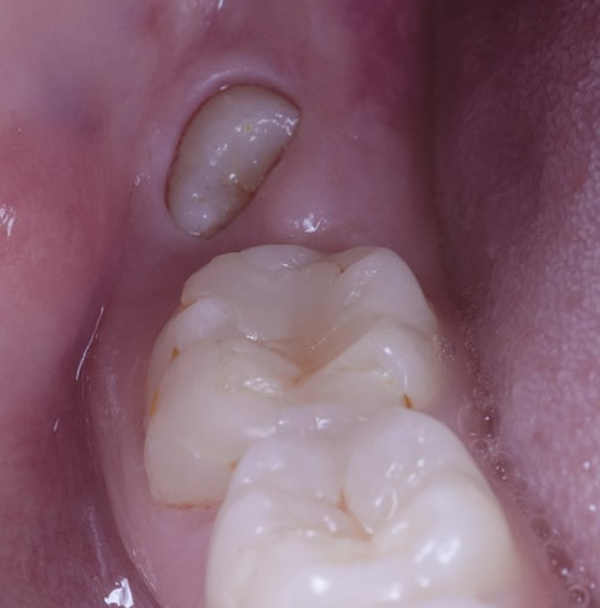

Ausencia de dientes

Porque estos nunca han llegado a desarrollarse.

Su diagnóstico lo llevamos a cabo en la consulta cuando el paciente presenta alguna de las siguientes situaciones:

Tras el proceso de cambio dentario, una o varias piezas no erupcionan.

En comparación con el resto de los dientes, todavía se mantienen las piezas de leche.